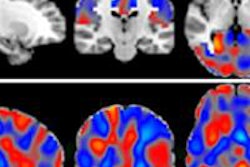

The current study looked at the effect on the hippocampus of chronic low-dose-rate radiation exposure of 1 mGy per day or 20 mGy per day over 300 days with cumulative doses of 0.3 Gy and 6.0 Gy, respectively. An apolipoprotein E (ApoE)-deficient mutant C57Bl/6 mouse served as an Alzheimer's model.

Mass spectrometry of the exposed mice detected a marked alteration in the phosphoproteome at both dose rates. The radiation-induced changes were associated with control of synaptic plasticity, calcium-dependent signaling, and brain metabolism, the authors wrote.

In addition, inhibition of CREB cellular transcription factor signaling was found at both dose rates, while Rac1-Cofilin signaling was activated only at the lower dose rate. Similarly, a reduction in the number of activated microglia in the molecular layer of hippocampus that paralleled reduced levels of tumor necrosis factor-alpha expression and lipid peroxidation was significant only at the lower dose rate.

Both dose rates in the study are capable of inducing molecular features that are reminiscent of those found in Alzheimer's disease neuropathology, Kempf and colleagues concluded.